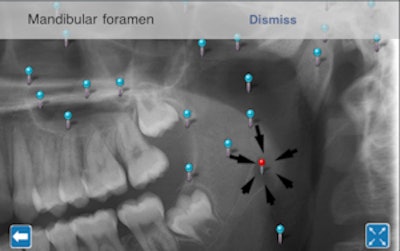

iPanoramic pinpoints key anatomical features in pano images.

ICBCT Anatomy has been so successful that Dr. Al-Rawi has developed a similar teaching tool: iPanoramic. This app, which was submitted to the iTunes app store on November 12 and is still awaiting approval, is designed to pinpoint key anatomical features in a panoramic image. When the user clicks on a pinpointed feature, a window pops up with the name of that feature. Ultimately, Dr. Al-Rawi and his colleague intend to add a button to the screen to provide more information about each feature, he said.